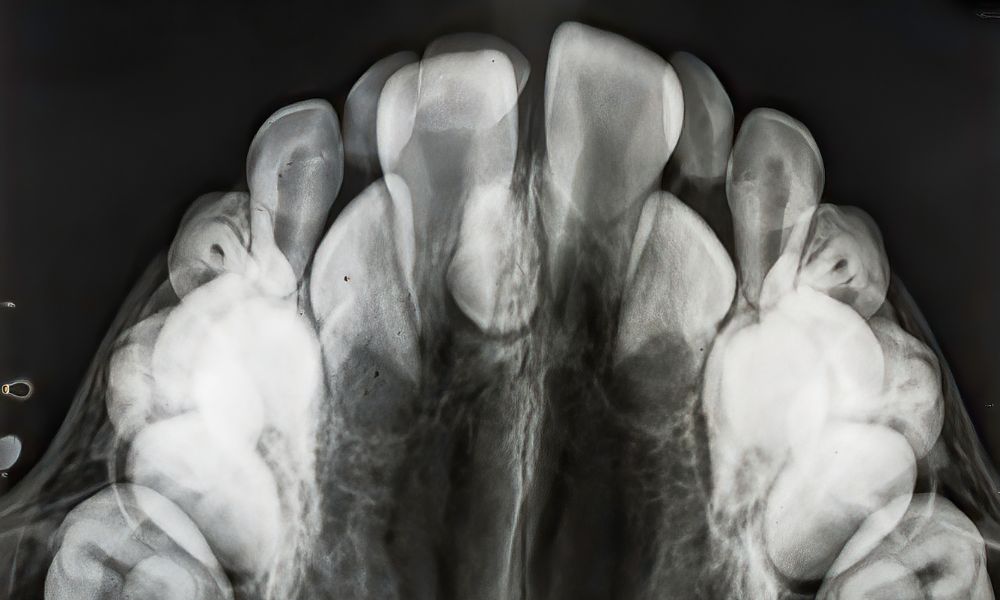

El rol de la radiografía en la detección

La radiografía panorámica es una herramienta esencial para detectar dientes supernumerarios, incluso cuando no han erupcionado. Este método permite visualizar la posición y el tamaño de los dientes adicionales, facilitando un diagnóstico preciso.

La detección temprana es clave para evitar complicaciones como el apiñamiento dental o la erupción irregular. Si sospechas que tienes dientes extras, consulta con un especialista para obtener un diagnóstico adecuado y un tratamiento personalizado.